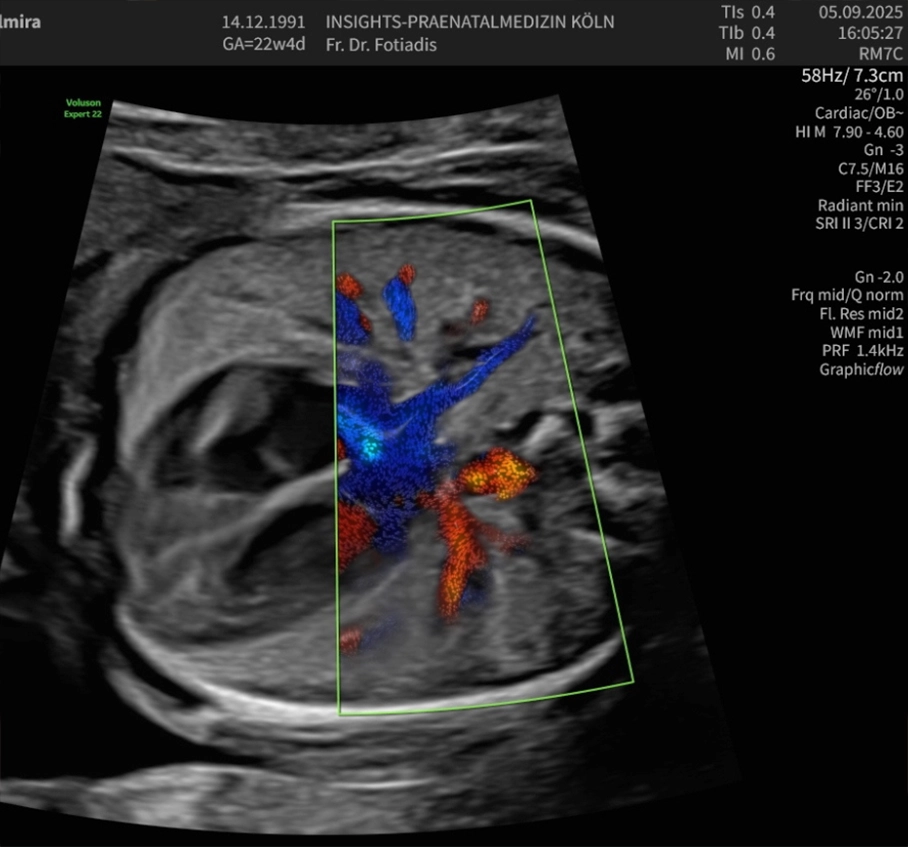

Diese spezielle Untersuchungsmethode dient der Überprüfung von Blutflüssen und Flussgeschwindigkeiten in der Gebärmutter und in verschiedenen kindlichen Blutgefäßen. Mittels Dopplersonographie sind wir in der Lage, die Blutversorgung wie auch die Herzfunktion und Kreislaufsituation des Kindes zu beurteilen. Ebenso kann eine fetale Anämie (Blutarmut) erkannt werden.

Die Beurteilung der mütterlichen Gebärmutterarterien erlaubt eine Abschätzung des Risikos für das Auftreten einer Schwangerschaftsvergiftung (Präeklampsie) oder einer Wachstumsstörung des Kindes. Auf diese Weise können wir die Versorgungslage und in gewissem Maße auch das kindliche Befinden überprüfen, Mangelversorgungen aufdecken und die entsprechenden Maßnahmen bis hin zur vorzeitigen Entbindung treffen.